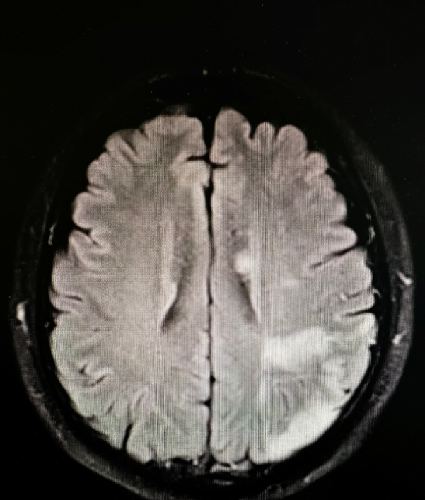

入院影像检查

导丝怎么扩【载药时代 球扩天下】NOVA DES®颅内药物洗脱支架在大脑中动脉重度狭窄中的应用两例!_https://www.jmylbn.com_新闻资讯_第5张

导丝怎么扩【载药时代 球扩天下】NOVA DES®颅内药物洗脱支架在大脑中动脉重度狭窄中的应用两例!_https://www.jmylbn.com_新闻资讯_第6张

重要影像结论DSA:左侧颈内动脉起始处重度狭窄、左侧大脑中动脉M1段偏心斑块伴重度狭窄。